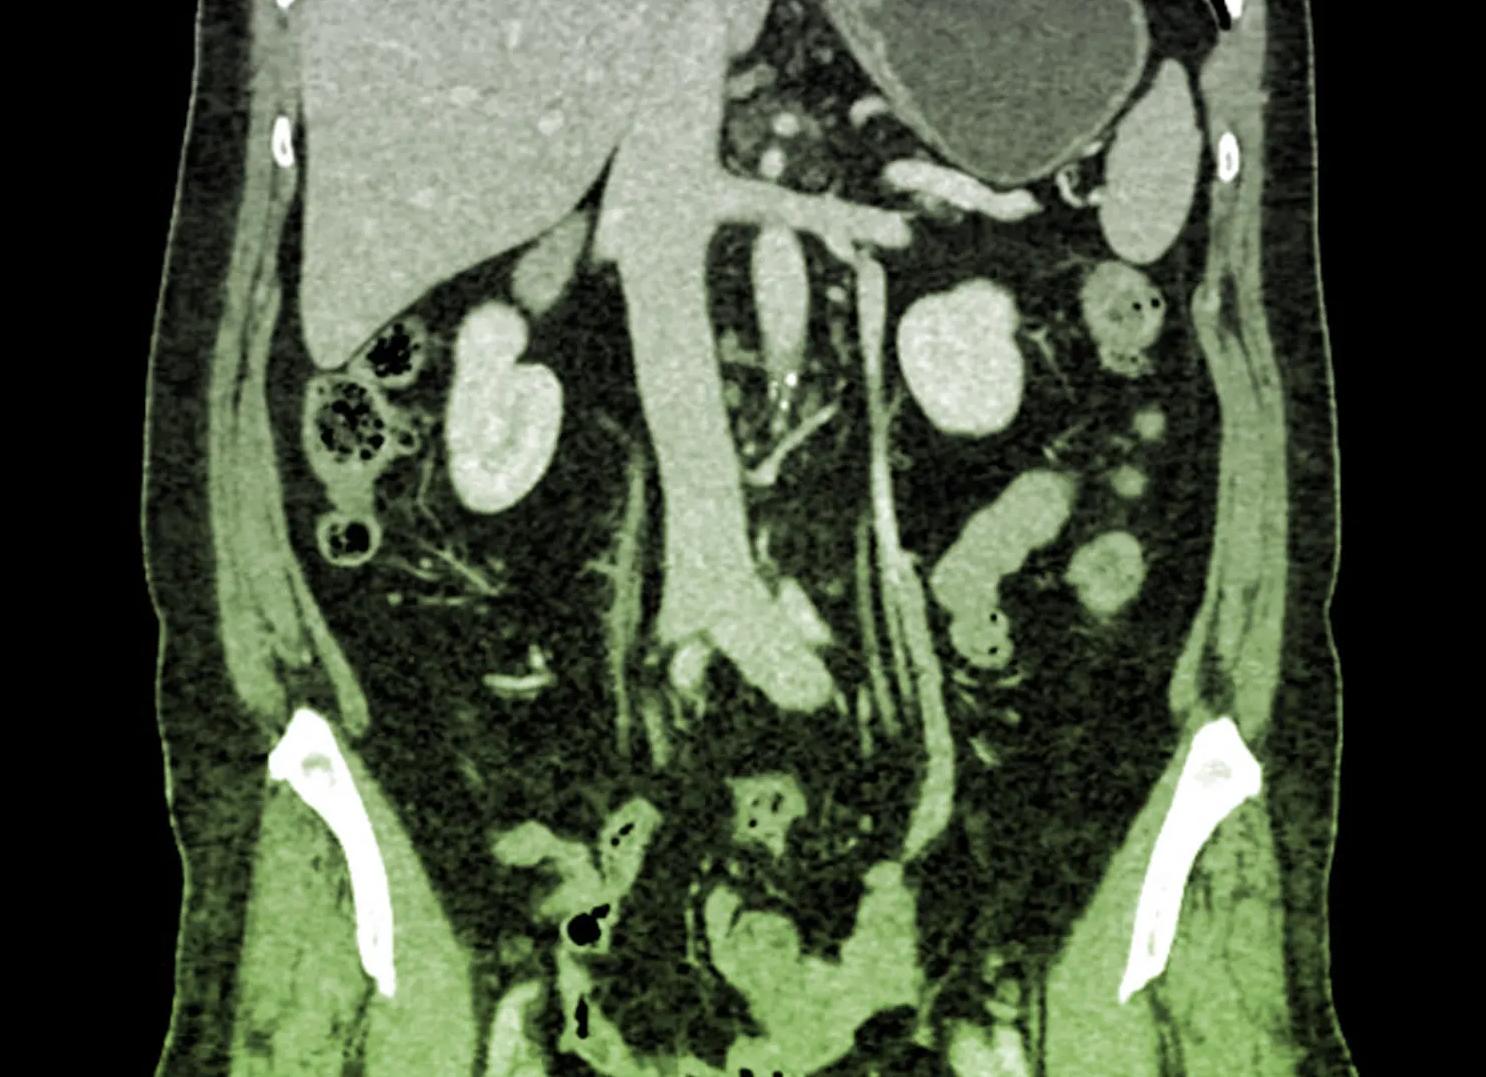

МРТ относится к распространенным способам исследования внутренних органов и тканей и получения тонких послойных срезов с их изображением. С помощью подобной диагностики выявляются патологии печени, селезенки, кишечника, половых органов, мягких тканей, сосудов и лимфоузлов.

Очень часто болезни внутренних половых органов совмещаются с патологиями кишечника, печени. Для поиска метастазов и мельчайших опухолей удобно проводить комплексное обследование пациента за один сеанс. Это облегчает поиски новообразований, нарушения кровотока в различных органах и тканях, участков с воспалением и гематомами. При необходимости можно исследовать и костные структуры, выявляя деструктивные изменения, нарушения в расположении позвонков, воспалительные процессы.

МРТ органов брюшной полости и малого таза проводится позволяет исследовать селезенку, поджелудочную железу, печень, желчный пузырь. Магнитно-резонансная томография показывает структуры, насыщенные водородом. Виден ли кишечник на МРТ, ведь в нем содержится воздух? При проведения исследования с контрастированием орган четко прослеживается. Магнитное сканирование забрюшиного пространства проводится при сочетании с исследованием малого таза. Врачей интересуют следующие органы:

МРТ брюшной полости – что показывает

Процедура позволяет выявить патологические изменения при наличии желтухи, тазовой боли, пожелтении белков глаз, необъяснимой лихорадке, частом повышении кровяного давления, отеках нижних конечностей. Процедура не назначается без особенной необходимости, несмотря на отсутствие радиационной нагрузки на пациента. Анализ дорогостоящий, поэтому без особой надобности не назначается. Показывает обследование дополнительное анатомическое образование (плюс-ткань) при наличии в нем клеток, содержащих атомы водорода. Контрастирование позволяет определить изменение структуры кишечника. При сдавлении стенки извне, образуется прогиб, который визуализируется при дополнительном контрасте.

Что показывает магнитно-резонансная томография брюшной полости:

1. Опухоли, дивертикулез, дополнительные образования внутри желудка, мочевого пузыря, поджелудочной железы, печени; 2. Кисты яичников, опухоли, миома матки, злокачественный рост предстательной железы у мужчин; 3. Заболевания печени, почек, селезенки; 4. Камни в желчном пузыре, желчевыводящих путей; 5. Сужение, расширение кровеносного сосуда; 6. Снижение мышечной силы после хирургических манипуляций, проблем с мочеиспусканием;

7. Врожденные дефекты (агенезия, аплазия мочеточников, почек).